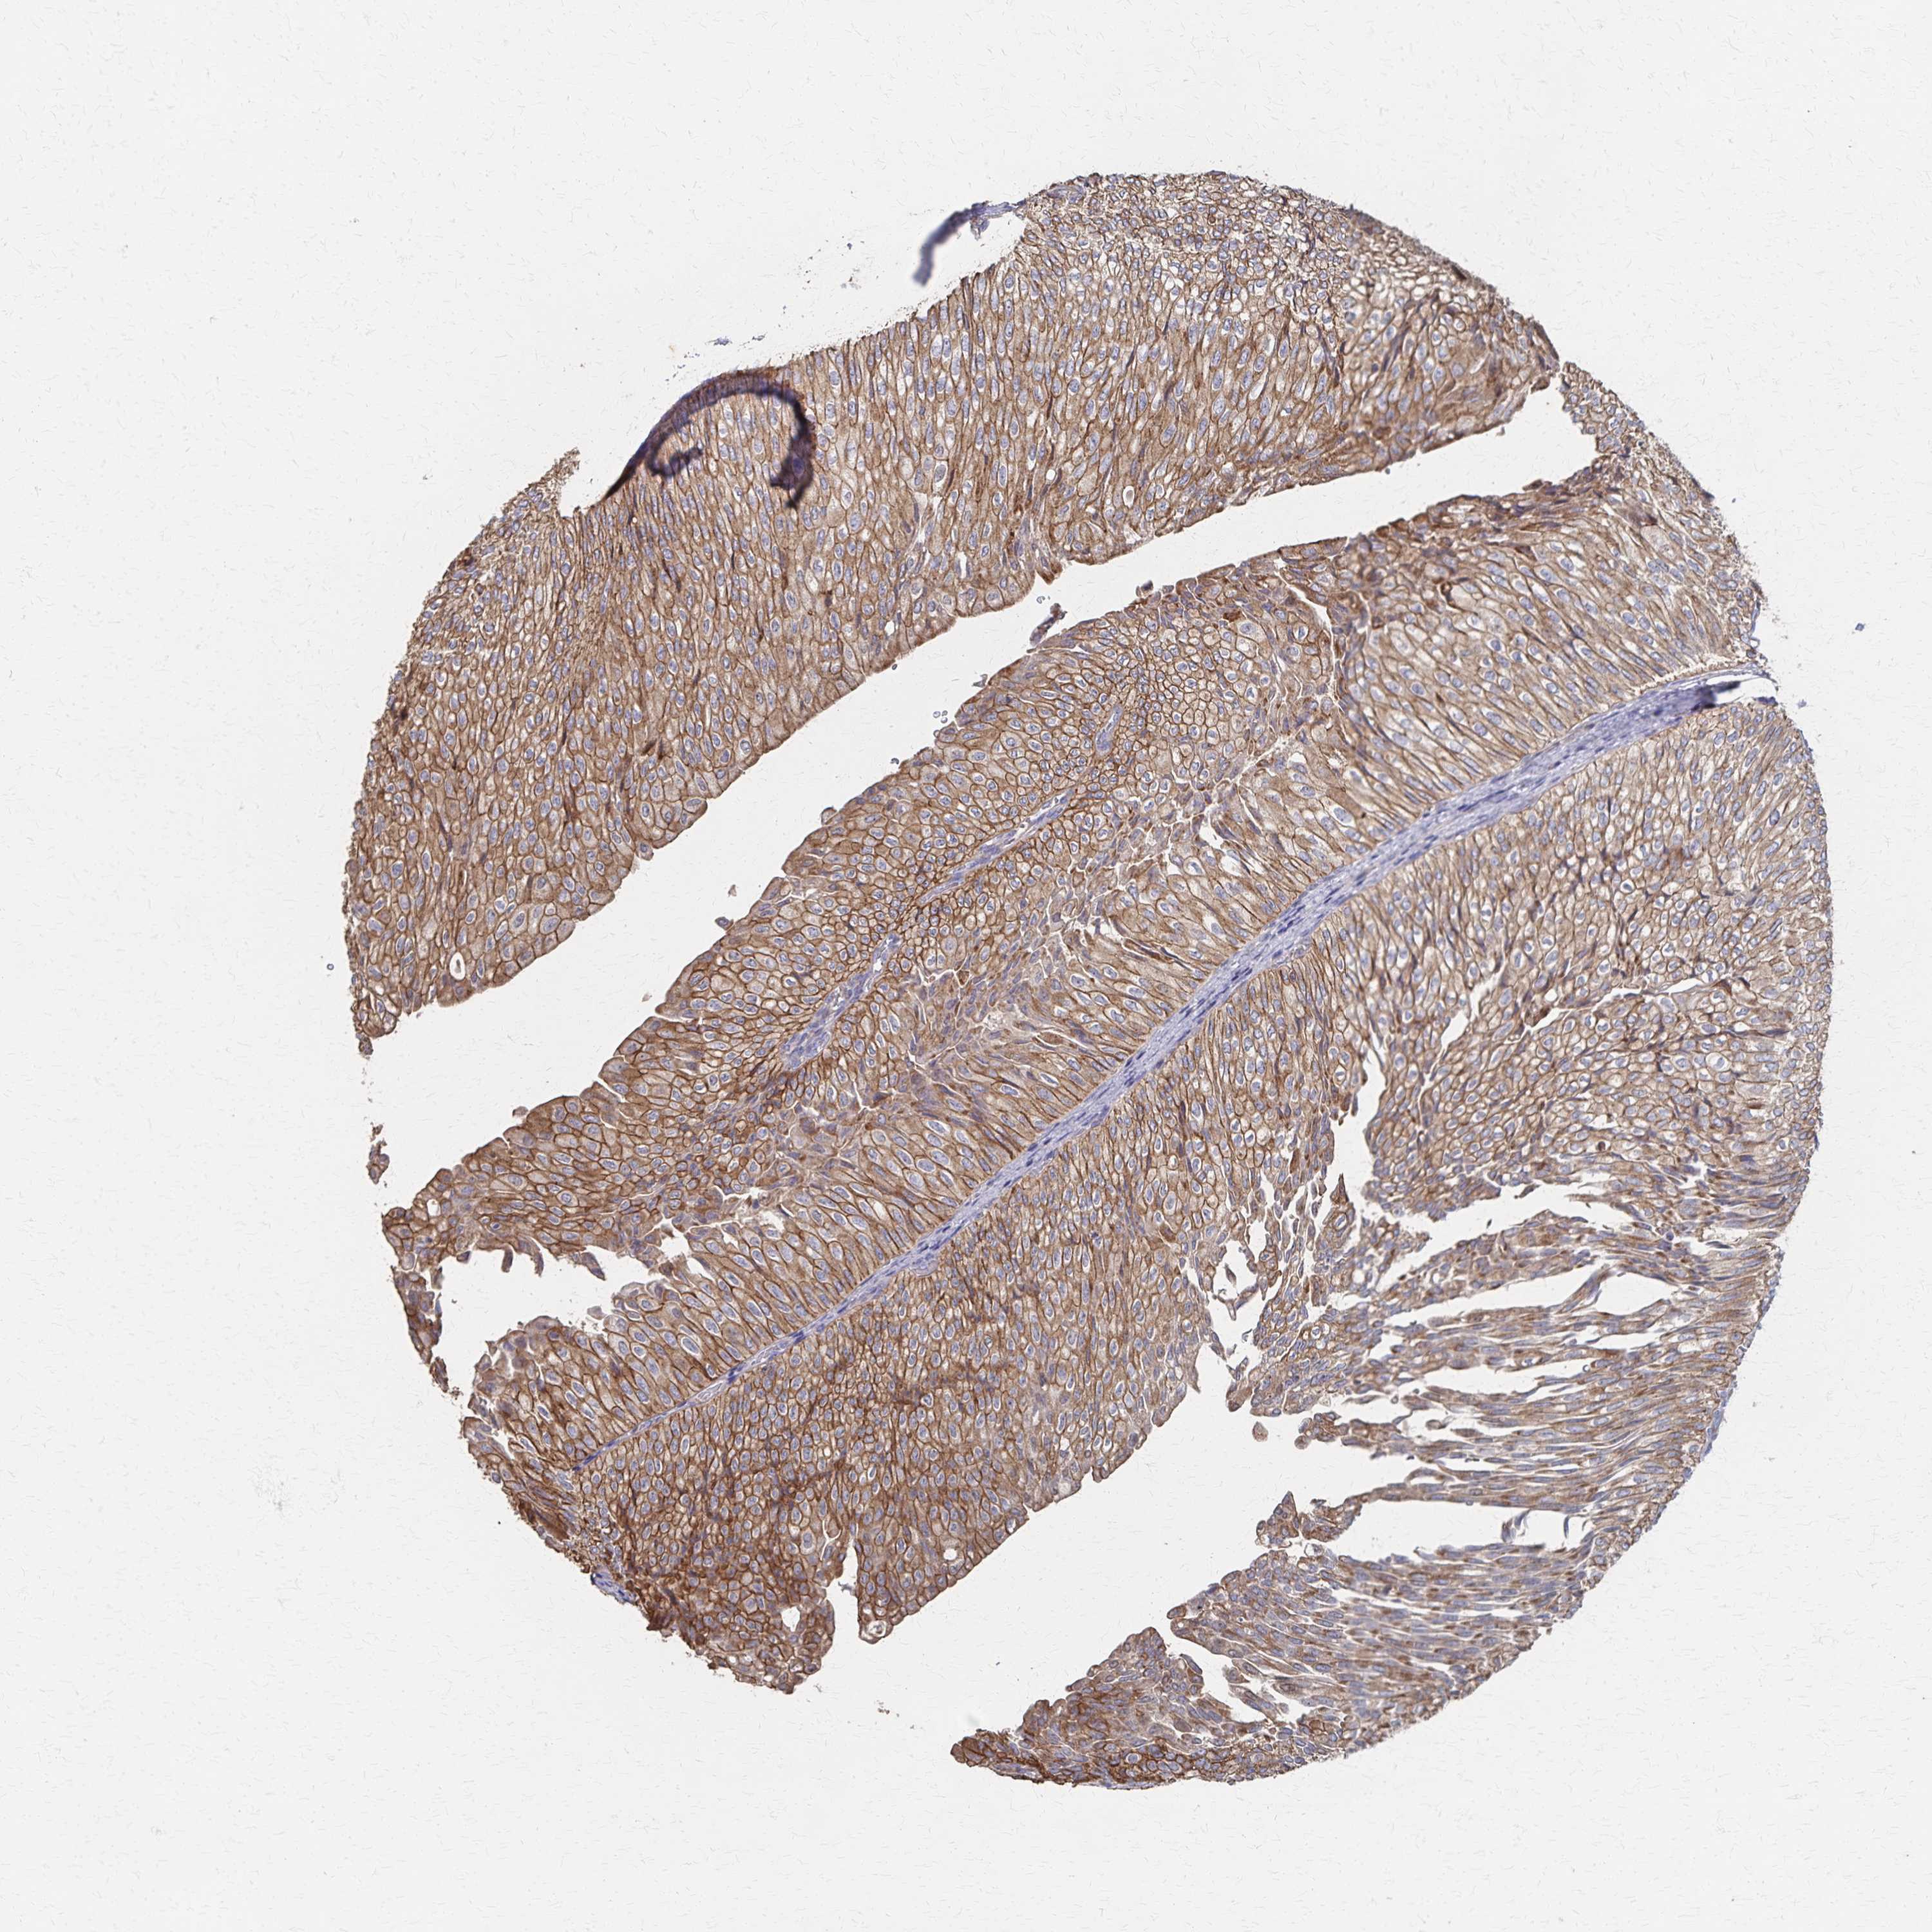

UROTHELIAL CANCER - Protein expressioni

A mouse-over function shows sample information and annotation data. Click on an image to view it in a full screen mode. Samples can be filtered based on level of antibody staining by selecting one or several of the following categories: high, medium, low and not detected. The assay and annotation is described here.

Note that samples used for immunohistochemistry by the Human Protein Atlas do not correspond to samples in the TCGA dataset.

Antibody stainingi

Antibody staining in the annotated cell types in the current human tissue is reported as not detected, low, medium, or high, based on conventional immunohistochemistry profiling in selected tissues. This score is based on the combination of the staining intensity and fraction of stained cells.

Each image is clickable and will lead to virtual microscopy that enables deeper exploration of all samples and also displays staining intensity scores, fraction scores and subcellular localization as well as patient and tissue information for each sample.

Antibody HPA063099

Staining

High

Medium

Low

Not detected

Intensity

Strong

Moderate

Weak

Negative

Quantity

>75%

75%-25%

<25%

None

Location

Nuclear

Cytoplasmic/membranous

Cytoplasmic/membranous,nuclear

Urothelial carcinoma, High grade

Urothelial carcinoma, NOS

Urothelial carcinoma, Low grade